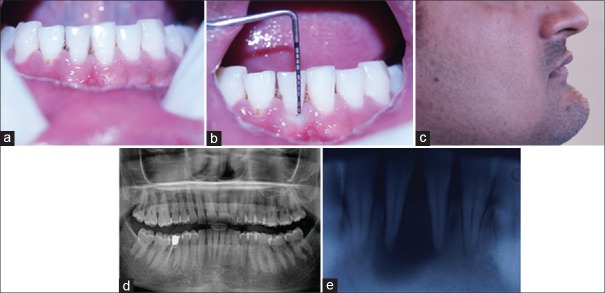

根管囊肿(RC)是影响颌骨的最常见的牙源性炎性囊肿,累及龋齿或外伤性非重要牙齿的根部。针对此类病变的治疗,人们提出了不同的治疗方法,如非手术牙髓治疗或带有原封闭、减压等功能的外科根管治疗。本病例是一名 28 岁的健康男性患者,他报告说 41 号牙、31 号牙和 31 号牙出现疼痛和肿胀。根据临床、放射学和细针穿刺细胞学检查,确诊为罕见部位的感染性 RC。考虑到临床特征、起源、延伸、囊性病变的大小和患者的合作情况,采用了巴斯克假说的非手术牙髓疗法。术后一年的结果表明,非手术牙髓治疗和利用巴斯克假说的微创治疗是将感染性根尖囊肿病变转化为健康根尖周牙周组织的有效工具。

Radicular cyst (RC) is the most common odontogenic cyst of inflammatory origin affecting the jaws; involves the roots of the carious or traumatic non-vital tooth. Different therapeutic modalities, such as nonsurgical endodontic therapy or surgical enucleation with primary closure, decompression etc., were proposed for the management of such lesions. Presenting a case of a 28-year-old otherwise healthy male patient who reported with pain and swelling with respect to tooth #41, 31. Diagnosis of infected RC at a rare location was established on the basis of clinical, radiographical and fine needle aspiration cytological examination. Looking after the clinical characteristics, origin, extension, size of cystic lesion and patient cooperation; nonsurgical endodontic therapy utilizing Bhasker's hypothesis was opted. One year post-operative result suggested that nonsurgical endodontic therapy along with minimally invasive treatment utilizing Bhasker's hypothesis is an effective tool to transform infected radicular cystic lesion to healthy periapical periodontal tissue.